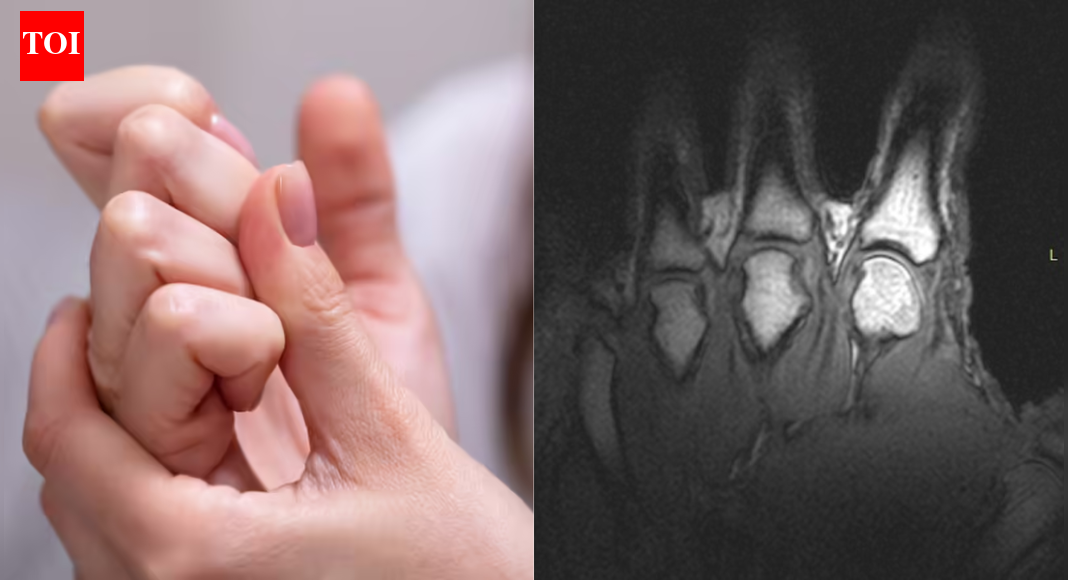

संशोधक आता सहमत आहेत की पोर, पायाची बोटं किंवा इतर सांधे तडकल्यावर निर्माण होणारा आवाज हाडे पीसणे किंवा कूर्चा तुटणे नव्हे तर वायूमुळे होतो. एक मोठ्या प्रमाणावर उद्धृत2015 चा अभ्यासकेवळ सिद्धांतावर अवलंबून न राहता सांधे तडकताना पाहण्यासाठी रीअल-टाइम एमआरआय इमेजिंगचा वापर केला, प्रक्रिया जशी घडली त्याप्रमाणे कॅप्चर केली.

स्कॅनमध्ये असे दिसून आले की जेव्हा एखादा सांधा ओढला जातो किंवा ताणला जातो तेव्हा सांध्याच्या आतील दाब अचानक कमी होतो. सायनोव्हियल फ्लुइड, सांध्यांना वंगण घालणारा निसरडा द्रव, वाढणारी जागा लवकर भरू शकत नाही. परिणामी, द्रव आत गॅसने भरलेली पोकळी तयार होते. या प्रक्रियेला ट्रायबोन्यूक्लिएशन म्हणून ओळखले जाते आणि त्या पोकळीच्या जलद निर्मितीमुळे विशिष्ट पॉपिंग आवाज निर्माण होतो.

बोटांच्या सांध्याला तडे गेल्याने वायूचा फुगा तयार होणारा MRIs शेजारी (अल्बर्टा विद्यापीठ)

अल्बर्टा विद्यापीठातील पुनर्वसन औषध विद्याशाखेतील प्राध्यापक ग्रेग कावचुक यांनी या प्रक्रियेचे सोप्या भाषेत वर्णन केले. विज्ञान सूचना.“जेव्हा तुम्ही असे करता तेव्हा, सांध्याच्या आत काय चालले आहे ते तुम्ही अगदी स्पष्टपणे पाहू शकता,” तो म्हणाला.“हे थोडेसे व्हॅक्यूम बनवण्यासारखे आहे. संयुक्त पृष्ठभाग अचानक विभक्त झाल्यामुळे, वाढत्या सांध्याचे प्रमाण भरण्यासाठी अधिक द्रव उपलब्ध नाही, त्यामुळे एक पोकळी तयार होते आणि ती घटना आवाजाशी संबंधित आहे.”या शोधाने 1970 च्या दशकातील पूर्वीच्या सिद्धांतांना खोडून काढले ज्याने असे सुचवले होते की आवाज तयार होण्याऐवजी वायूचे फुगे कोसळल्याने होतो.